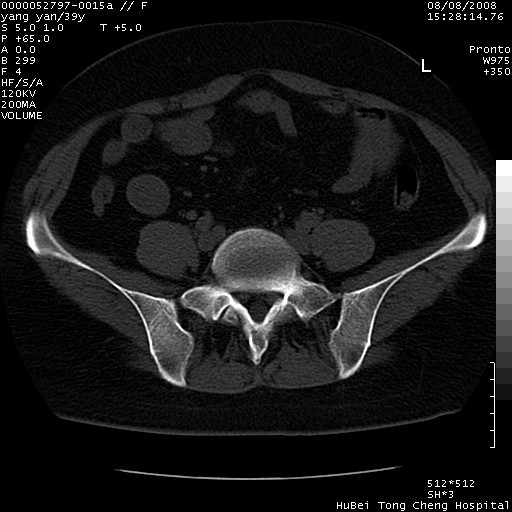

患者 女,39岁。因外伤检查,偶然发现。

典型!双侧骶髂关节致密性骨炎。

典型!病变主要累及双侧髂骨。常见于育龄期妇女。

致密性骨炎,一般不跨越关节面,可是这个骶骨关节面也有硬化。

髂骨致密性骨炎系一种以骨质硬化为特点的非特异性炎症,有高度致密的骨硬化现象,尤其以髂骨下2/3更为明显,但关节间隙则无改变。因位于骶髂关节,且该关节症状明显,故又称之为“骶髂关节致密性骨炎”。 本病90%以上为中年女性,以妊娠后期、尤其分娩后为多见,亦可见于尿路或女性附件慢性感染后,或盆腔内其他感染。此外,臀骶部的外伤亦可诱发或引起本病。  妊娠、分娩及外伤均可引起骶髂关节韧带的撕裂而易使局部的血供受阻。因此早期局部呈现充血、水肿及渗出增加等,渐而局部出现增生与变性反应,随着胶原纤维的致密化而向硬化演变;血管形成厚壁血管,易闭塞而引起髂骨耳状面处缺血和缺氧,骨质呈现硬化性改变,以致手术时局部出血较少。骶髂关节囊壁显示纤维增生、弹性降低及松动样改变。继发于盆腔内炎症者亦出现相类似的病理改变,可能系细菌内毒素作用所致。